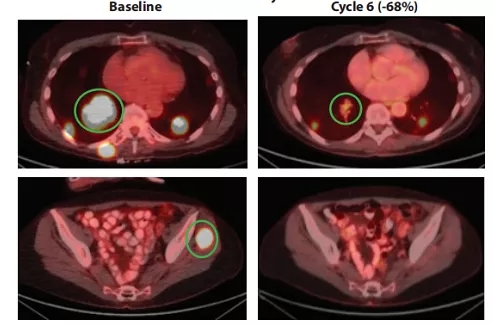

68岁的A女士2017年确诊为NTRK融合晚期甲状腺癌,接受全身化疗后,2019年2月开始160 mg QD的剂量使用repotrectinib,第6周肿瘤缩小68%。